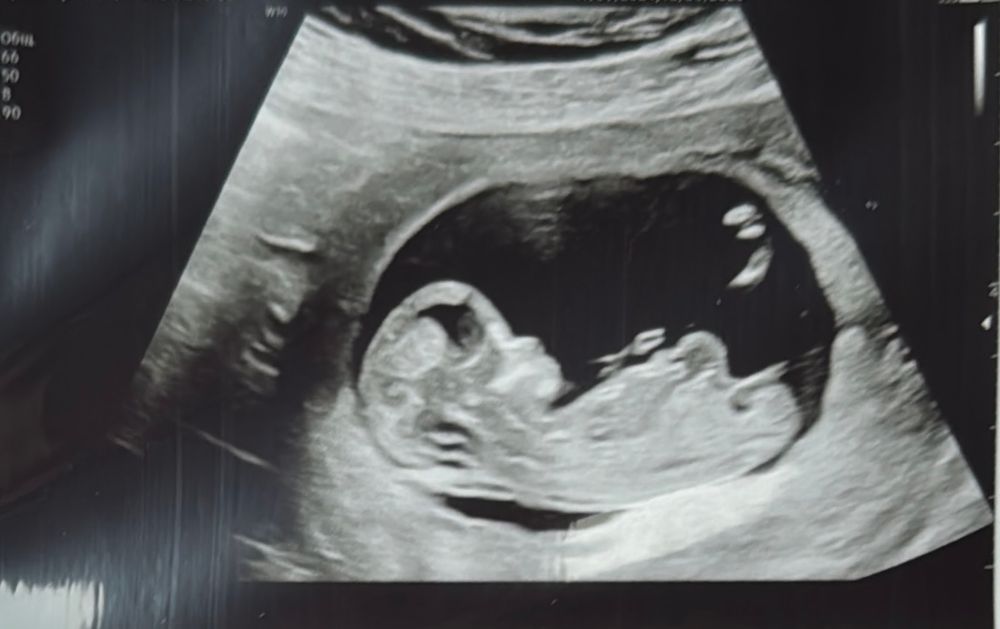

Тоже недавно совсем мониторила по скринингу какой пол у малыша может быть) так похоже на девочку ) и мне подтвердили , у меня кстати похоже фото скрининга ) Вроде если мальчик то бугорок смотрит выше Изображение

08.12.2024

Katrinrina, да, больше на девочку похож, но я видела у одной женщины точно такое же узи как у вас и у меня, и у нее был мальчик, на 20 неделе подтвердили ей, так что жду тоже этого срока, чтобы быть точно уверенной в поле будущего малыша ))